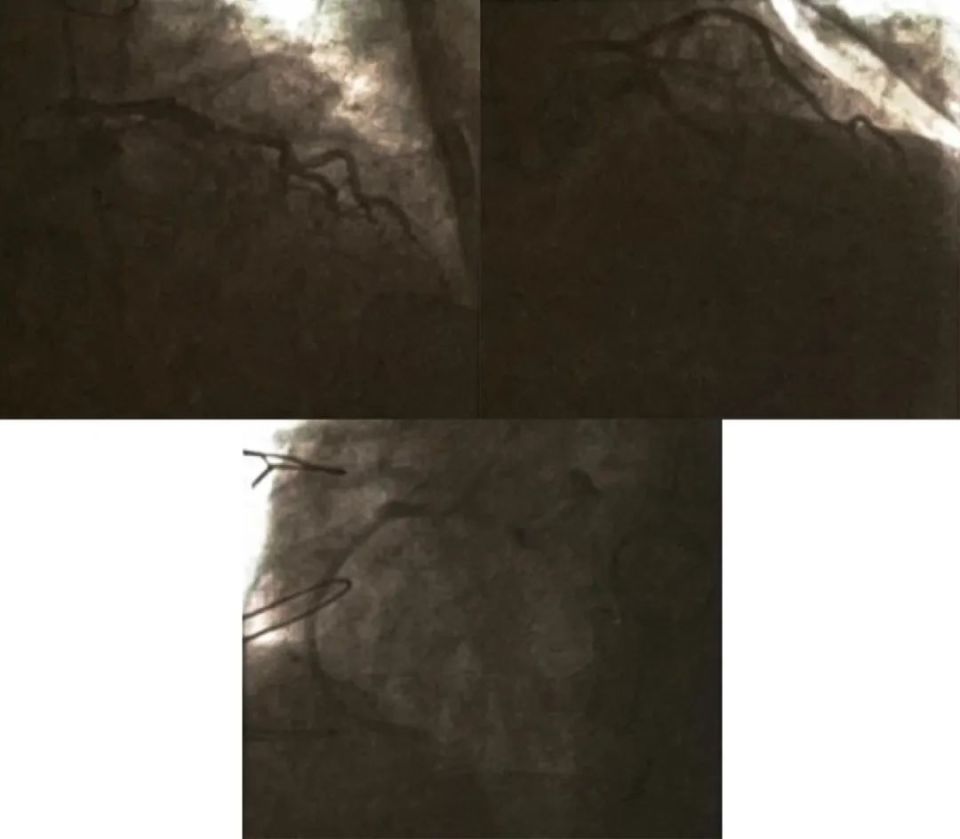

急诊冠状动脉造影提示左前降支(LAD)、左回旋支(LCX)未见明显狭窄,右冠状动脉(RCA)近中段未见斑块浸润,远段完全闭塞。行急诊冠状动脉介入治疗(PCI 术),术中导丝顺利通过病变到达左心室后支(PL)远端,行血栓抽吸,抽吸后血栓负荷依然很重,后用球囊(2.5 mmx20 mm)进行扩张。扩张后血流能够到达PL远端,而且可见后降支(PD)开口,但后三叉血栓负荷依然较重,再次进行血栓抽吸。操控第二根导丝通过PD,送入球囊(1.5 mmx15 mm)进行扩张成形。后送入支架(Resolute Integrity 3.0 mmx26 mm)至右冠状动脉远端,PD球囊保护,右冠状动脉支架扩张成形,同时与PD球囊进行对吻。随后用非顺应性球囊(3.2 5mmx12 mm)扩张成形支架,术后右冠状动脉远端血流可,PD血流差,TIMI血流I~Ⅱ级。术后收治心脏重症监护室。(图1)

图1. 入院急诊冠状动脉造影PCI

肝位示LCX未见狭窄病变;正位+头示LAD未见狭窄病变;左前斜位示RCA近中段血管正常,远段血栓性闭塞